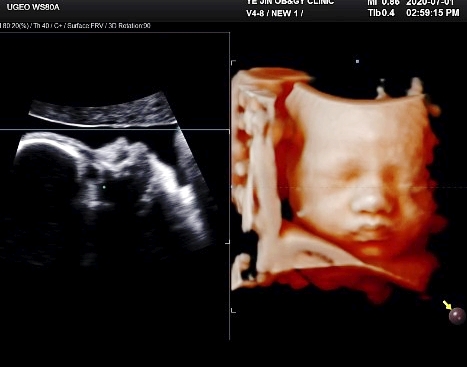

33+3 / D-33